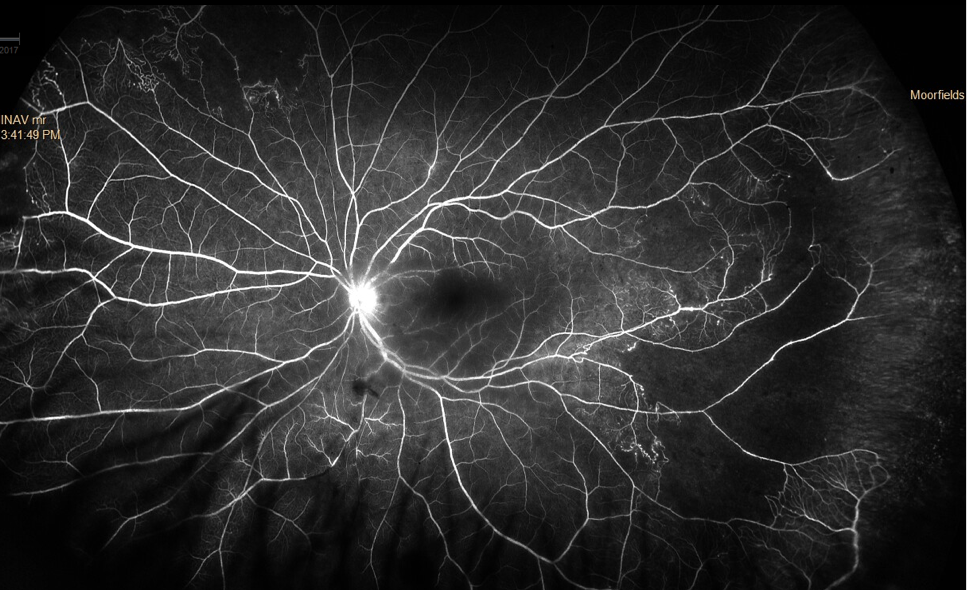

Write your caption hereButton Write your caption here

Write your caption here